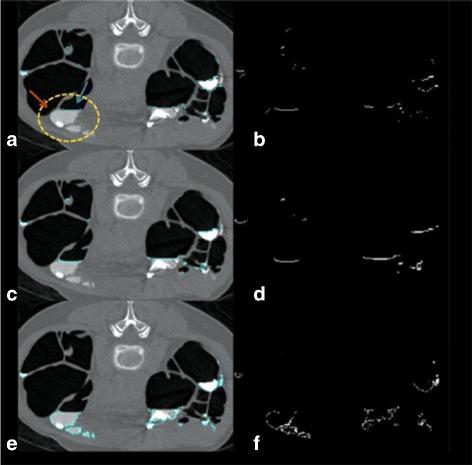

In computed tomography colonography images, electronic cleansing (EC) is applied to remove opacified residual materials, called fecal-tagging materials (FTM), using positive-contrast tagging agents and laxative to facilitate polyp detection.

METHODS

The proposed EC, EC , integrates the gradient directional second derivative into material fraction model to preserve submerged soft tissue (ST) under FTM. Three-material fraction model is used to remove FTM and artifacts at air-tagging (AT) layers and T-junctions where air, ST, and FTM material meet simultaneously. Moreover, the proposed AT layer identification is used to distinguish AT layers from air-tissue-tagging (ATT) layers in order to preserve ATT layers during cleansing. The clinical evaluation on 467 3-Dimensional band view images was conducted by the abdominal radiologist using four grading levels of cleansing quality with five causes of low quality EC. The amount of the remaining artifacts at T-junctions was approximated from the results of EC . The results from EC were compared with the results from syngo.via Client 3.0 Software, EC , and the fast three-material modeling, EC , using the preference of the radiologist. Two-tailed paired Wilcoxon signed rank test is used to indicate statistical significance.

RESULTS

The average grade on cleansing quality is 2.89 out of 4. The artifacts at T-junctions from 86.94% of the test images can be removed, whereas artifacts at T-junctions from only 13.06% of the test images cannot be removed. For 13.06% of the test images, the results from EC are more preferable to the results from EC (p<0.008). For all the test images, the results from EC are more preferable to the results from EC (p<0.001). Finally, the visual assessment shows that EC can preserve ATT layers, submerged polyps and folds while EC can preserve only submerged folds but fails to preserve ATT layers.

CONCLUSION

From our implementation, EC can improve the performance of the existing EC, such that it can preserve ST, especially ATT layers and remove the artifacts at T-junctions which have never been proposed by any other methods before.